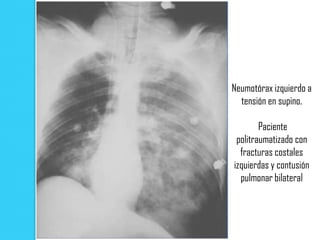

Neumotórax izquierdo a

tensión en supino.

Paciente

politraumatizado con

fracturas costales

izquierdas y contusión

pulmonar bilateral

Neumotórax izquierdo a tensión en supino. Paciente politraumatizado con fracturas costales izquierdas y contusión pulmonar bilateral